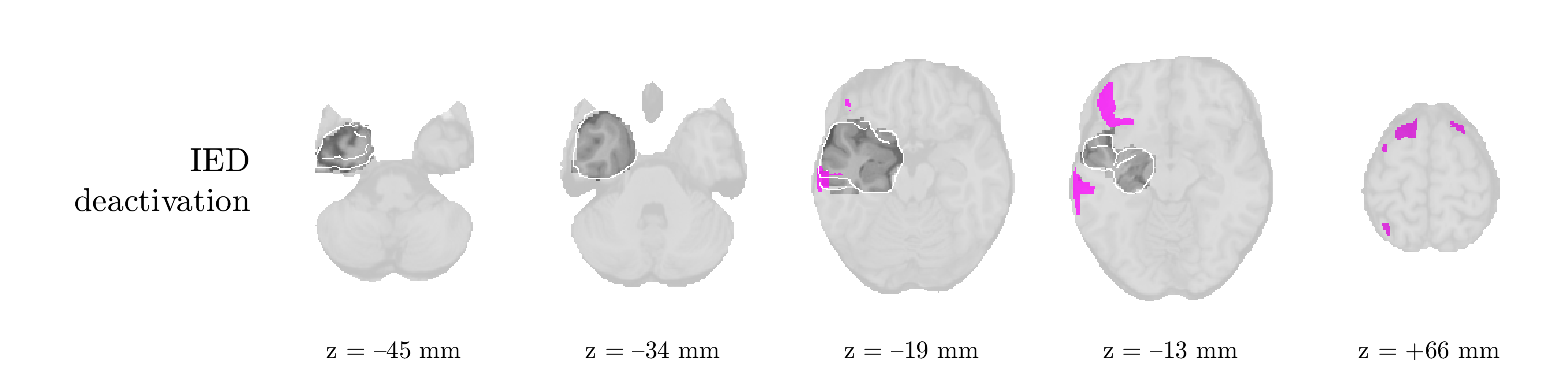

Patient 1

We analyze the solution with sources. Figure 1 shows the EEG signatures and HRF waveforms. One of the sources is highly correlated to the MWF reference (in grey), which was already known from Table B.3. This IED-related source had a typical low-frequency spectrum, which is expected for the typical spike-and-wave interictal discharges. The topography is relatively diffuse, although the highest amplitudes are mostly in the left hemisphere. This is in accordance with the lateralization of ictal onset zone (left temporal lobe, cfr. Table 1). There are some noteworthy observations to be made about some of the other components. The fourth has an unusually sharp spectrum, is mainly localized on two nonadjacent center electrodes, and is sustained for a single period of many seconds Hence, this component likely captured an artifact (of yet unknown origin), although we spotted no large-amplitude changes in the EEG itself. Similarly, the third source is only present at one frontal electrode, and exists in a frequency range above 20 Hz. It might represent a muscle artifact, e.g., due to frowning or twitching of some muscles in the forehead. The HRFs of all ROIs are shown in Figure 1(b). Two of the basis functions seem to have converged to a very similar waveform, which is an unfortunate possibility if two initial HRFs are too close to the same local optimum in their respective parameters. This reduces the expressive power of the basis set, which is clearly visible, since many ROIs have a nearly identical HRF. One of the twenty ROIs with the highest-entropy HRF overlapped the IOZ, although clearly this HRF (bold line) is not among the most dissimilar waveforms for this patient. This is also visible in Figure 2: both the HRF entropy and extremity maps show a small overlap with the delineated IOZ. Despite the good correspondence in the EEG domain, no significant (de)activation of the IED-component is found inside the IOZ.